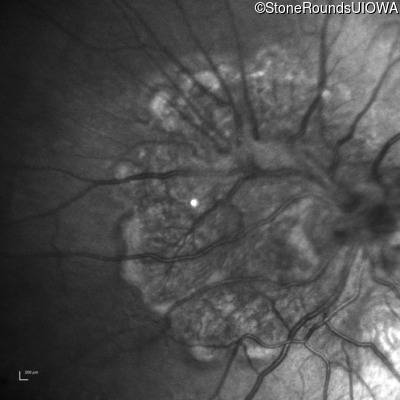

Infrared Fundus Photograph - Right - 20/2000

Exemplar